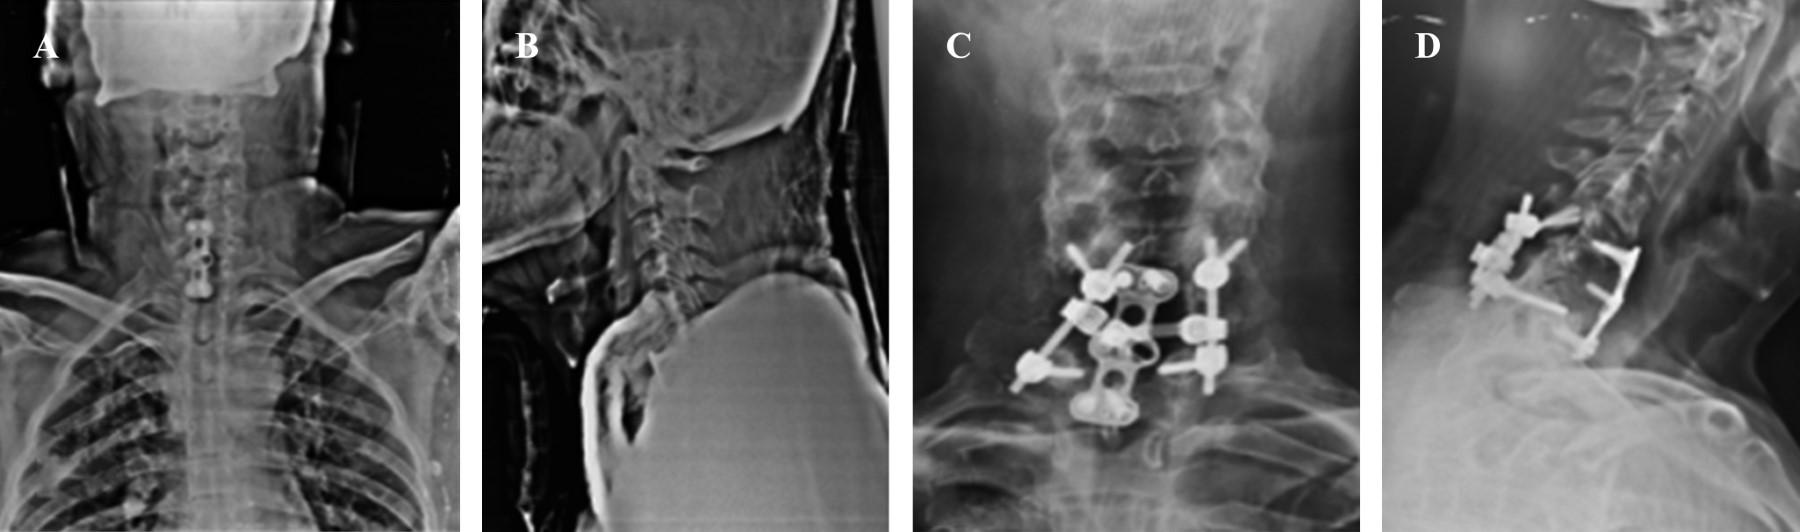

Se programa primer tiempo quirúrgico para realizar hemicorpectomía C7, discectomía C7-T1, espondilodesis con placa anterior dos niveles C6-C7, C7-T1, más toma y aplicación de injerto de cresta ilíaca, se corrobora resultado mediante TAC. Se realiza segundo tiempo quirúrgico siete días posteriores de primera intervención realizando abordaje cervical posterior + fascetectomías de C7 + fijación transfacetarias C6 y transpedicular de T1 con tornillos, barras y un cross-link (Figura 4).

La toma de decisiones con respecto al manejo por vía anterior versus vía posterior de una luxación cervical es relevante;1,13,14,15 para nuestro paciente se decidió realizar el primer tiempo quirúrgico por vía anterior para retirar completamente el disco afectado y de esta forma evitar la compresión medular con el mismo antes de realizar el abordaje posterior. El objetivo final de cualquiera de los procedimientos es obtener una reducción anatómica, descompresión medular y evitar inestabilidad con una fusión adecuada. Los tratamientos informados de la espondiloptosis han incluido abordaje anterior con o sin instrumentación y fusión posterior y anterior. Se planificó estabilización más fijación anterior y fusión en el primer tiempo quirúrgico. En la siguiente etapa se programó la instrumentación posterior y la fusión para lograr la estabilización. Se logró la reducción total confirmándose con Rx y TAC de control con una evolución clínica (Figura 5) satisfactoria del paciente.